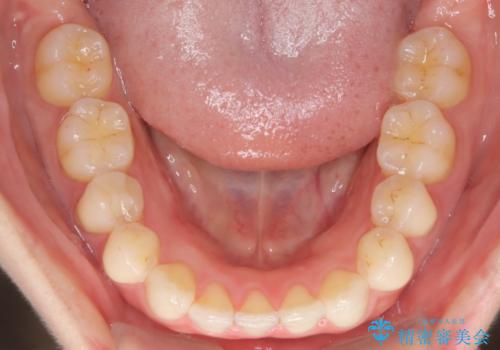

- 下顎前歯の叢生を主訴に来院されました。

臼歯関係の状態から下顎前歯一本の抜歯を行う治療計画を立て、インビザラインを使用して治療を行いました。

今回の抜歯ケースはインビザラインでも綺麗に治ります。